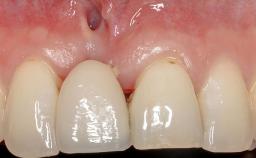

A 30-year-old woman was referred by her general dentist for evaluation of an esthetic complication related to previous implant treatment for congenitally missing maxillary lateral incisors. The patient’s chief complaint was the inadequate esthetic appearance of her smile. The case demonstrates the use of a combined approach to achieve optimal results. Two different flap designs - a tunnel technique and a coronally advanced flap - are employed based on the surgical objectives for the affected site.

Soft Tissue Grafting Yes